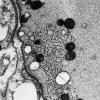

Giant Axonal Neuropathy (GAN) (6)